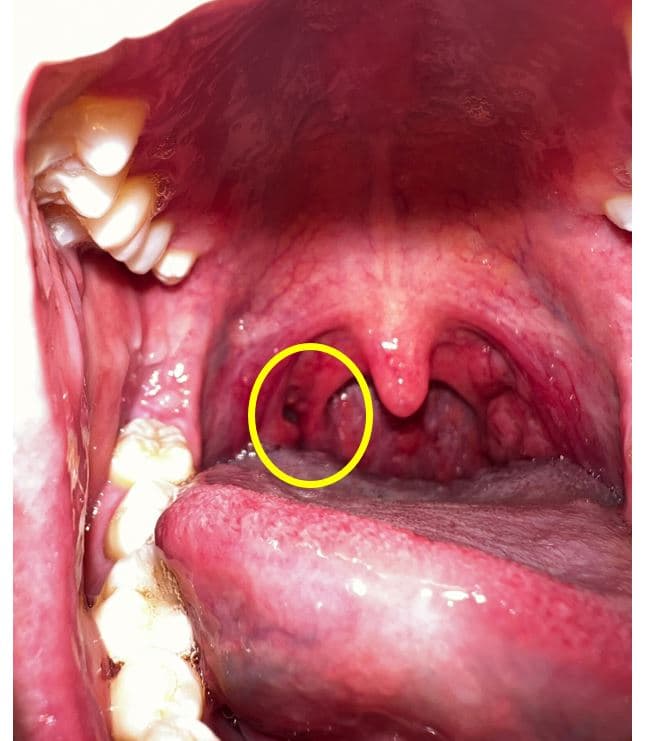

어느순간부터 편도쪽에 이질감과 함께 편도결석의 악취가 느껴져 핸드폰으로 촬영을 해봤습니다.

확인결과 목구명 편도 쪽에(아래사진의 목구멍편도 좌측 구멍) 구멍이 있습니다.

이상없을까요 ?